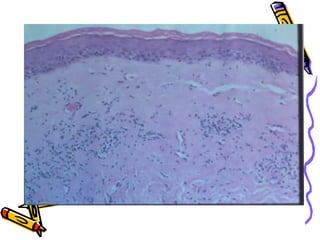

This document discusses benign and malignant diseases of the vulva. It begins by outlining common symptoms of vulvar diseases such as itching, burning, and bleeding. It then provides an overview of the general pathology and terminology used to describe vulvar diseases. The document categorizes vulvar lesions as white, red, or brown/bluish and discusses specific conditions that present with each color, including vitiligo, lichen sclerosis, squamous cell hyperplasia, infections, dermatitis, and various precancers and cancers. Treatment options are provided for some conditions like HPV. Throughout, it emphasizes the importance of inspection, palpation, biopsy prior to treatment, and using medical therapy for benign lesions.